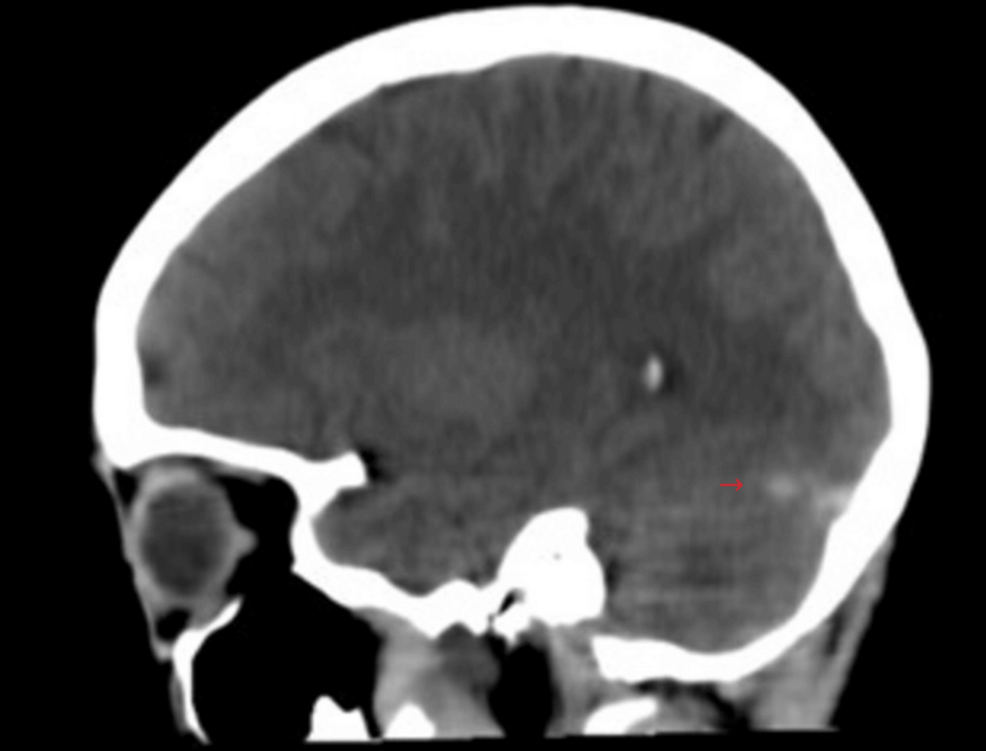

- The article includes a medical image, suggesting a focus on health-related issues.

- The mention of “Specialty” implies a healthcare context, connecting to SDG 3.